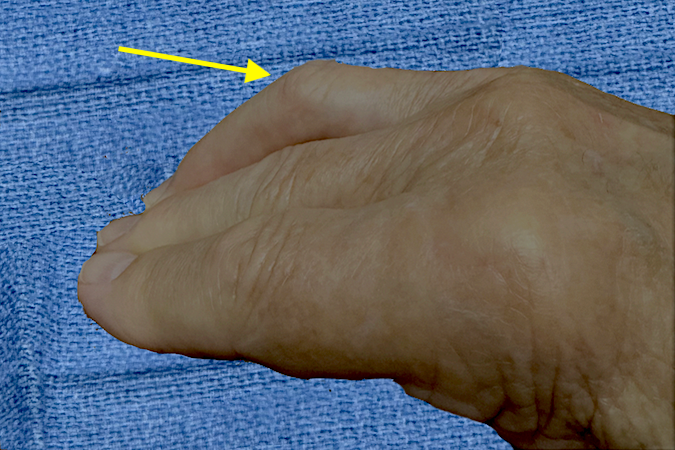

• Chronic righr ring trigger finger in right handed 65 y.o. male.  Note the chronic secondary PIP joint mild flexion contracture (arrow).

Chronic righr ring trigger finger in right handed 65 y.o. male. Note the chronic secondary PIP joint mild flexion contracture (arrow).